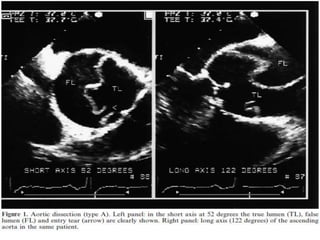

 Aortic dissection is a clinical emergency that is challenging to diagnose.

 TEE and CT angiography are the two most commonly employed imaging

modalities for aortic dissection.

 Multiple studies have demonstrated the high sensitivity and specificity of

both modalities for diagnosing type A dissections.

 The sensitivity and specificity of TEE have been reported as 90% to 100%

and 94% respectively .